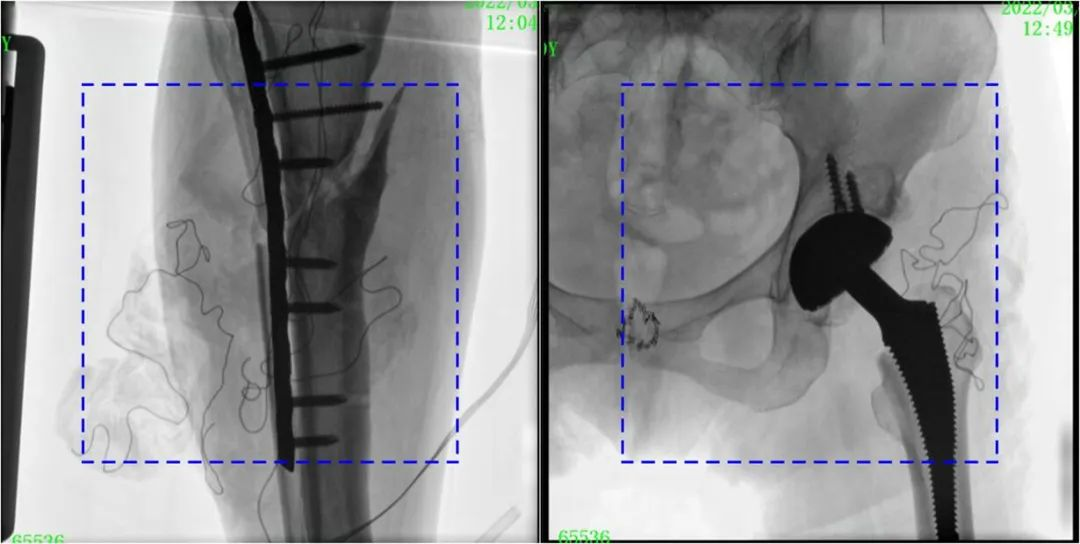

与传统的21CM×21CM成像尺寸相比,糖心vlog 大平板一体式C形臂具有30CM×30CM更大成像尺寸,能够一次成像5.5节椎体,呈现更全面的影像信息,即便是手术经验不丰富的年轻医生也能通过图像迅速判断椎体节段、定位手术部位,避免因为视野不足而造成的多次定位、反复曝光,提高效率的同时避免过量摄入辐射。

糖心vlog 大平板一体式C形臂图像与传统图像对比(蓝色虚线内为传统21CM×21CM平板的成像区域)